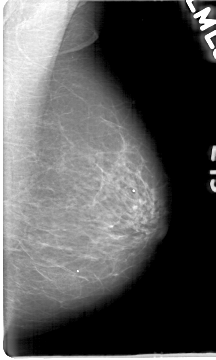

D_4068_1.RIGHT_CC

LEFT_CC LINES 5386 PIXELS_PER_LINE 3136 BITS_PER_PIXEL 12 RESOLUTION 43.5 NON_OVERLAY